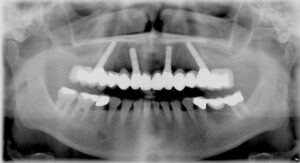

Röntgenbild mit 4 Implantaten und festsitzender Implantatbrücke im Oberkiefer. Beachte die 2 hintern schräg eingesetzten Implantate zum Ausnutzen des Knochenangebots unterhalb der Kieferhöhle (Sinuslift wird vermieden).

Tatsächlich hat sich dieses Versorgungskonzept als nachhaltig erwiesen. Es hat den Vorteil, dass die feste Brücke auf 4 Implantaten auch dann möglich ist, wenn im Seitenzahnbereich ein nicht seltener Knochenmangel besteht. Die Kosten bleiben durch die aufwändigere 3D-Planung ähnlich hoch, wie bei der „klassischen“ Implantatbrücke auf 6 Implantaten.